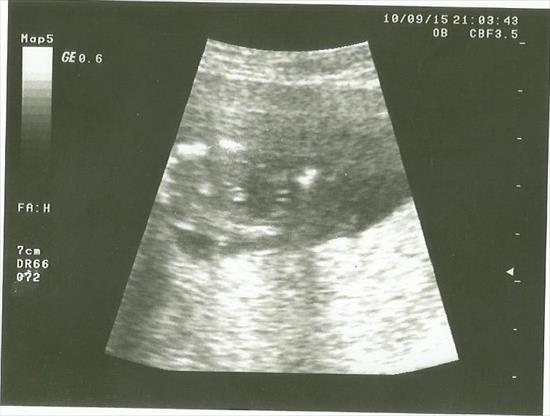

hello again here is my nub pictures from12week Attachment 27501Attachment 27502Attachment 27503 so what do you think and this my potty picture from 15week i have posted thank you!!Attachment 27504

Boy from potty shot!